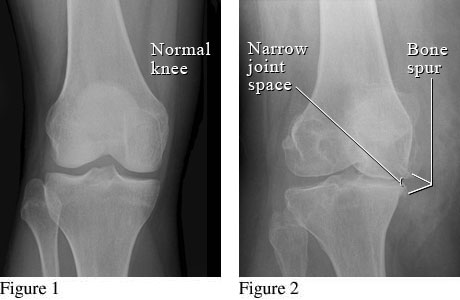

Osteoarthritis (OA) dapat digambarkan sebagai degradasi dan hilangnya kartilago sendi disertai dengan remodeling subchondral, pembentukan osteofit dan sinovitis. Penyebab dari osteoarthritis adalah adanya penekanan beban tubuh yang secara terus menerus terhadap persendian, sehingga mengakibatkan kerusakan terhadap tulang rawan sendi. Akibat lanjutnya akan dapat menimbulkan beberapa masalah diantaranya nyeri karena terjepitnya ujung-ujung saraf sensoris oleh osteofit yang terbentuk serta adanya pembengkakan dan penebalan jaringan lunak di sekitar sendi yang akan mengakibatkan deformitas, terlepasnya osteofit pada suatu gerakan menimbulkan krepitasi pada sendi tersebut.